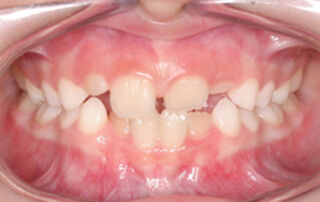

Caso clínico mordida cruzada anterior Placa Progenie – 02

Mordida cruzada anterior con incisivos inferiores proinclinados y tratado con una placa de progenie. Paciente con 6 años de edad que presenta una mordida cruzada anterior dental (MCAD). En las imágenes intraorales iniciales observamos la mordida cruzada anterior a nivel de los incisivos centrales. En la radiotelegrafía lateral de cráneo [...]